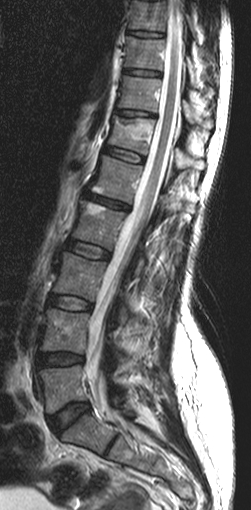

• In spinal truma CT is useful for localization of bone fragments, while MRI can visualize soft tissue structures within the spinal canal and discoligamentous injuries..

3.Back pain and decreased anal sphincter tone after motor accident. Left panel: Acute fracture of the 12th thoracic vertebra on CT. Right panel: Edema as a sign of acute fracture in the 12th thoracic vertebra on sagittal T2WI.

When examining the spine, it is important to decide that the injury is stable or unstable. AO classification of fractures should be used avoid miscommunication. This includes the evaluation of the intervertebral discs and the ligaments which are better appreciated with an MR study and provide extra information for surgical planning. MR studies are also necessary in cases where the CT scan cannot explain acute neurological symptoms because the state of the myelon, traumatic disc herniation and intraspinal haematomas can be only detected with MR.